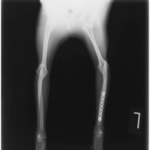

ペルシャ猫 11ヶ月齢 雄

他院にて左大腿骨遠位の成長板骨折(salter-harrisⅠ型)が認められており、治療相談を目的として来院。当院にて、キルシュナーワイヤーを用いたピンニングにより骨折部位の整復を行いました。術後の経過は良好で、現在も経過観察中です。

術前レントゲン

Arthrex社のターゲティングデバイスを用いてピンニングの位置を調整することで、確実な固定を行っています。当院ではこの手術器具以外にも、人の手術にも使用される様々な器具を導入し、手術精度を高め、また医療メーカーと新しい器具の開発、試作にも取り組んでおります。